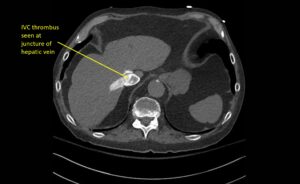

Wolff A, et al. Right atrial thrombosis. CT axial, juncture of hepatic vein

Wolff A et al. Right atrial thrombosis. CT axial juncture of hepatic vein